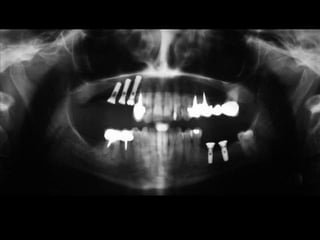

RADIOGRAFÍAS PANORÁMICAS